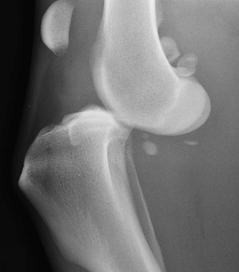

Complete stifle dislocation, also known as a ‘deranged stifle.’